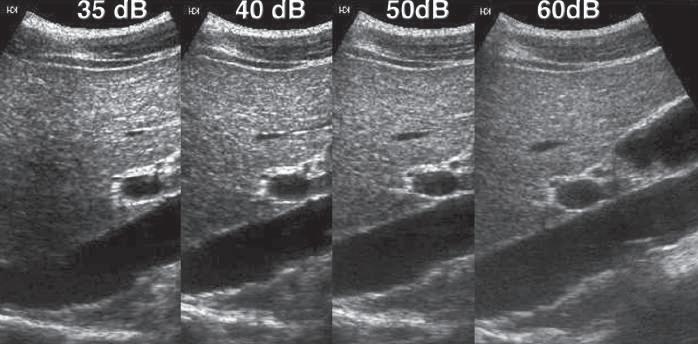

Another important function of the receiver is the compression of the wide range of amplitudes returning to the transducer into a range that can be displayed to the user. The ratio of the highest to the lowest amplitudes that can be displayed may be expressed in decibels and is referred to as the dynamic range. In a typical clinical application, the range of reflected signals may vary by a factor of as much as 1 : 1012, resulting in a dynamic range of up to 120 dB. Although the amplifiers used in ultrasound machines are capable of handling this range of voltages, gray-scale displays are limited to display a signal intensity range of only 35 to 40 dB. Compression and remapping of the data are required to adapt the dynamic range of the backscattered signal intensity to the dynamic range of the display (Fig. 1.11). Compression is performed in the receiver by selective amplification of weaker signals. Additional manual postprocessing controls permit the user to map selectively the returning signal to the display. These controls affect the brightness of different echo levels in the image and therefore determine the image contrast.

for the way the dynamic range of the target is compressed for display, as well as the transfer function that assigns a given signal amplitude to a shade of gray. Although these technical details vary among machines, the way the operator uses them may greatly affect the clinical value of the final image. In general, it is desirable to display as wide a dynamic range as possible, to identify subtle differences in tissue echogenicity (see Fig. 1.11).